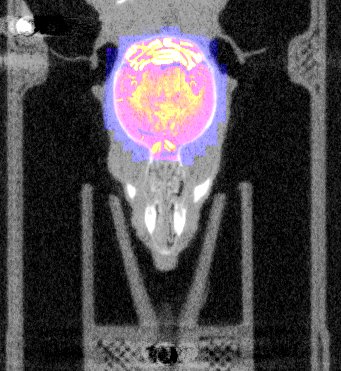

| Overlay of co-aligned CT scan and brain atlas-staining | Overlay of co-aligned CT scan and DAPI-staining | Overlay of co-aligned brain Atlas and DAPI-staining |